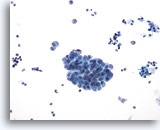

Urine obtenue par cathétérisme, résultat négatif

Les groupes de cellules sont souvent détruits par le cathétérisme.

20x

Urine obtenue par cathétérisme, résultat négatif

Les groupes de cellules sont souvent détruits par le cathétérisme.

20x